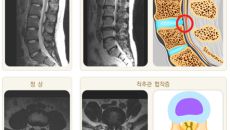

추운 겨울만 되면 속 불편하더니…이유 있었다

[이데일리 이순용 기자] 울산북구에 거주하는 50대 가정주부 A씨는 최근 소화가 잘 안되고 속 쓰림 증상이 계속되어 혹시나 하- 2026.02.07 14:21